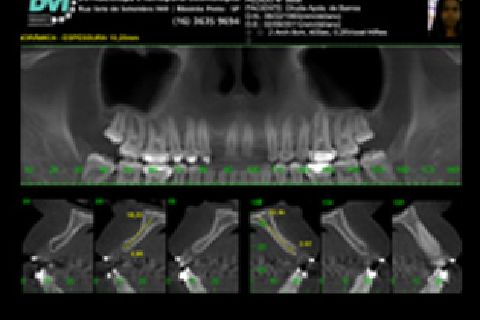

''Neste caso, a paciente gostaria de melhorar a estética do seu sorriso, prejudicada pela agenesia de ambos os incisivos laterais superiores. Devido à baixa disponibilidade óssea, observada na tomografia computadorizada, optou-se pela instalação de implantes estreitos (Xive – Dentsply Implants – 3.0 mm de diâmetro) com regeneração simultânea (Biooss e Biogide – Geistlich), ao invés de realizar enxerto ósseo prévio. Após osseointegração, foi realizado condicionamento gengival com provisórios e novo enceramento diagnóstico. O caso foi finalizado com coroas livres de metal sobre os implantes e microlaminados cerâmicos sobre os incisivos centrais (e.max - dissilicato de lítio – Ivoclar Vivadent), visando o mínimo desgaste de estrutura dental sadia. ''